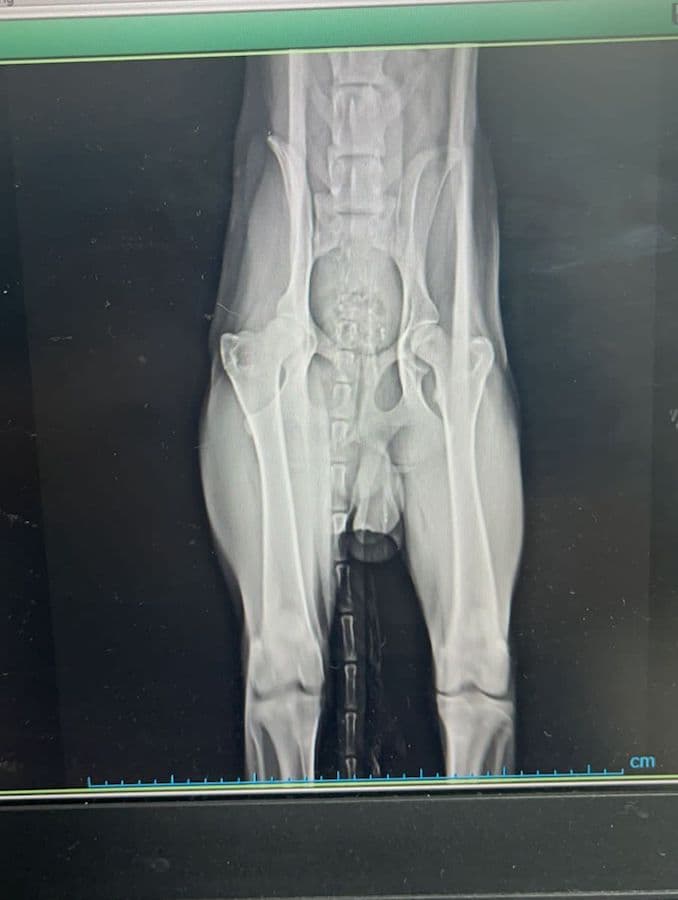

Biscotto (deutsch: Keks) ist etwa zwei Jahre alt und wurde am 20.10.2021 als Streuner am Stadtrand von Tirana in Albanien angefahren gefunden. Ein engagierter Tierschützer brachte ihn in die örtliche Tierklinik, wo er untersucht und geröntgt wurde. Dabei stellte sich heraus, dass seine Wirbelsäule gebrochen und der hinterer Teil seines Körpers gelähmt ist. Glücklicherweise zeigten die Untersuchungen keine Verletzungen der inneren Organe. Mittlerweile – 2 Wochen später – gibt es gute Entwicklungen: Biscotto kann wenn er im Freien ist, selbstständig Urin und Kot absetzen. Seine Hinterbeine zeigen etwas Aktivität. Manchmal schiebt und zieht er sie bei Bewegung zurück und er kann für einige Sekunden auf allen vier Beinen stehen! Er ist ein fröhlicher, freundlicher Hund der Aufmerksamkeit und Pflege braucht, die er in Albanien nicht erhalten kann, zumal es dort keine spezialisierten Einrichtungen für Tiere mit Handicap gibt. Aktuell lebt er in einem Käfig und es wird verzweifelt ein Zuhause oder eine Unterkunft gesucht. Wir leisten Vermittlungshilfe und hoffen so, dass der junge Rüde einen Platz findet. Interessenten melden sich bitte bei: Videos und weitere Fotos gibt es auf der facebook-Seite (in italienischer Sprache) für die Adoptionskampagne von Biscotto: